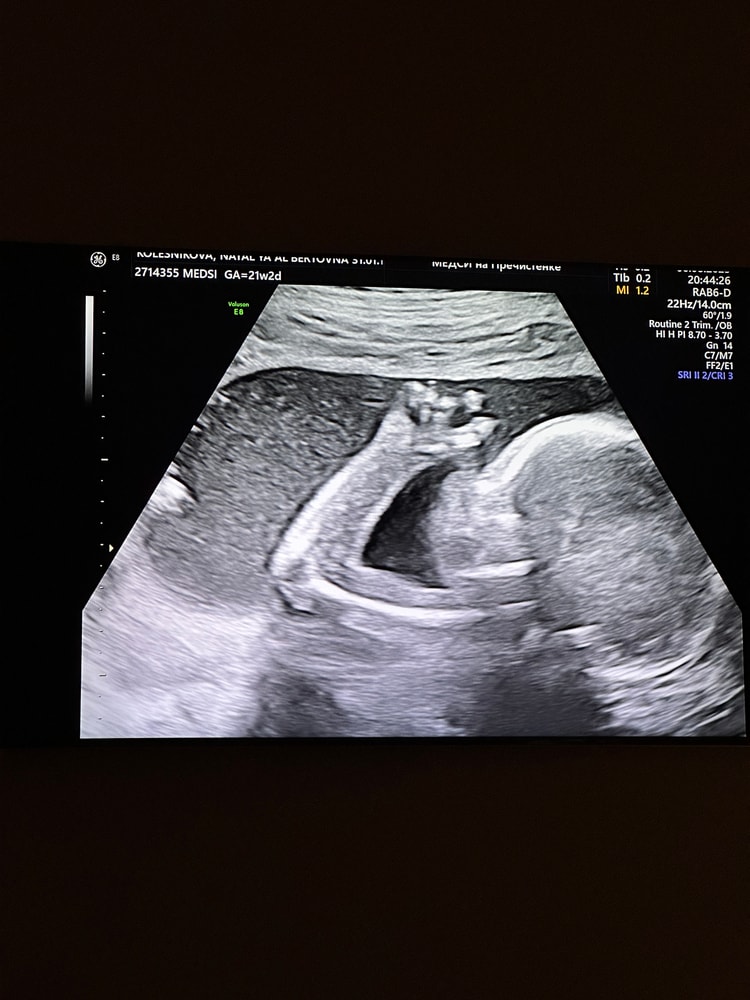

Совсем здесь пропала, но мне есть чем поделиться. Сейчас у меня 24 недели и 5 дней, в 21+2 были вместе с мужем на узи (впервые на совместном) - показали нам мальчишку достаточно подробно. Ну а что - свидания теперь вот такие :) Вообще еле его поймали, потому что утыкался личиком в плаценту и не могли в 3д его сфоткать, но в итоге ближе уже к концу и с третьей попытки - поймали :) крошечка, как же мы ждем тебя!

А вот и крошка 🧡